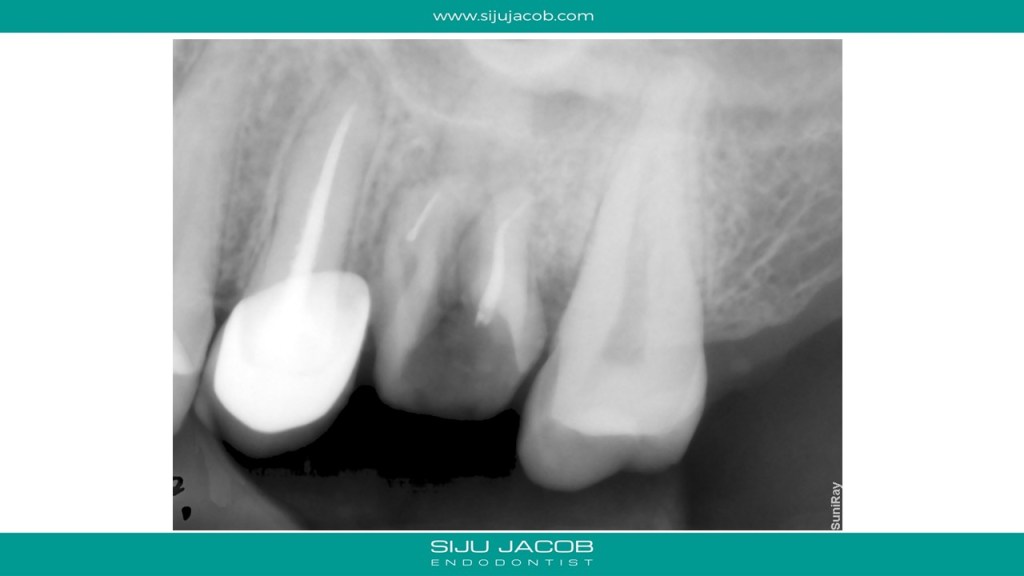

I told her to drop in for a consultation with me. Two months later, i get another mail telling me that her dentist had placed new crowns in both the teeth, but she was still not comfortable. The dentist had then offered to call in another specialist to re-do the root canal in one of the teeth. He had started the Re-root canal procedure, but the pain was still not gone. Could I have a look? She finally landed in my clinic and this is what i saw. And hence the title of the post: Oh No!

(Btw, I referred her to a neurologist and her diagnosis was Myofascial pain.)